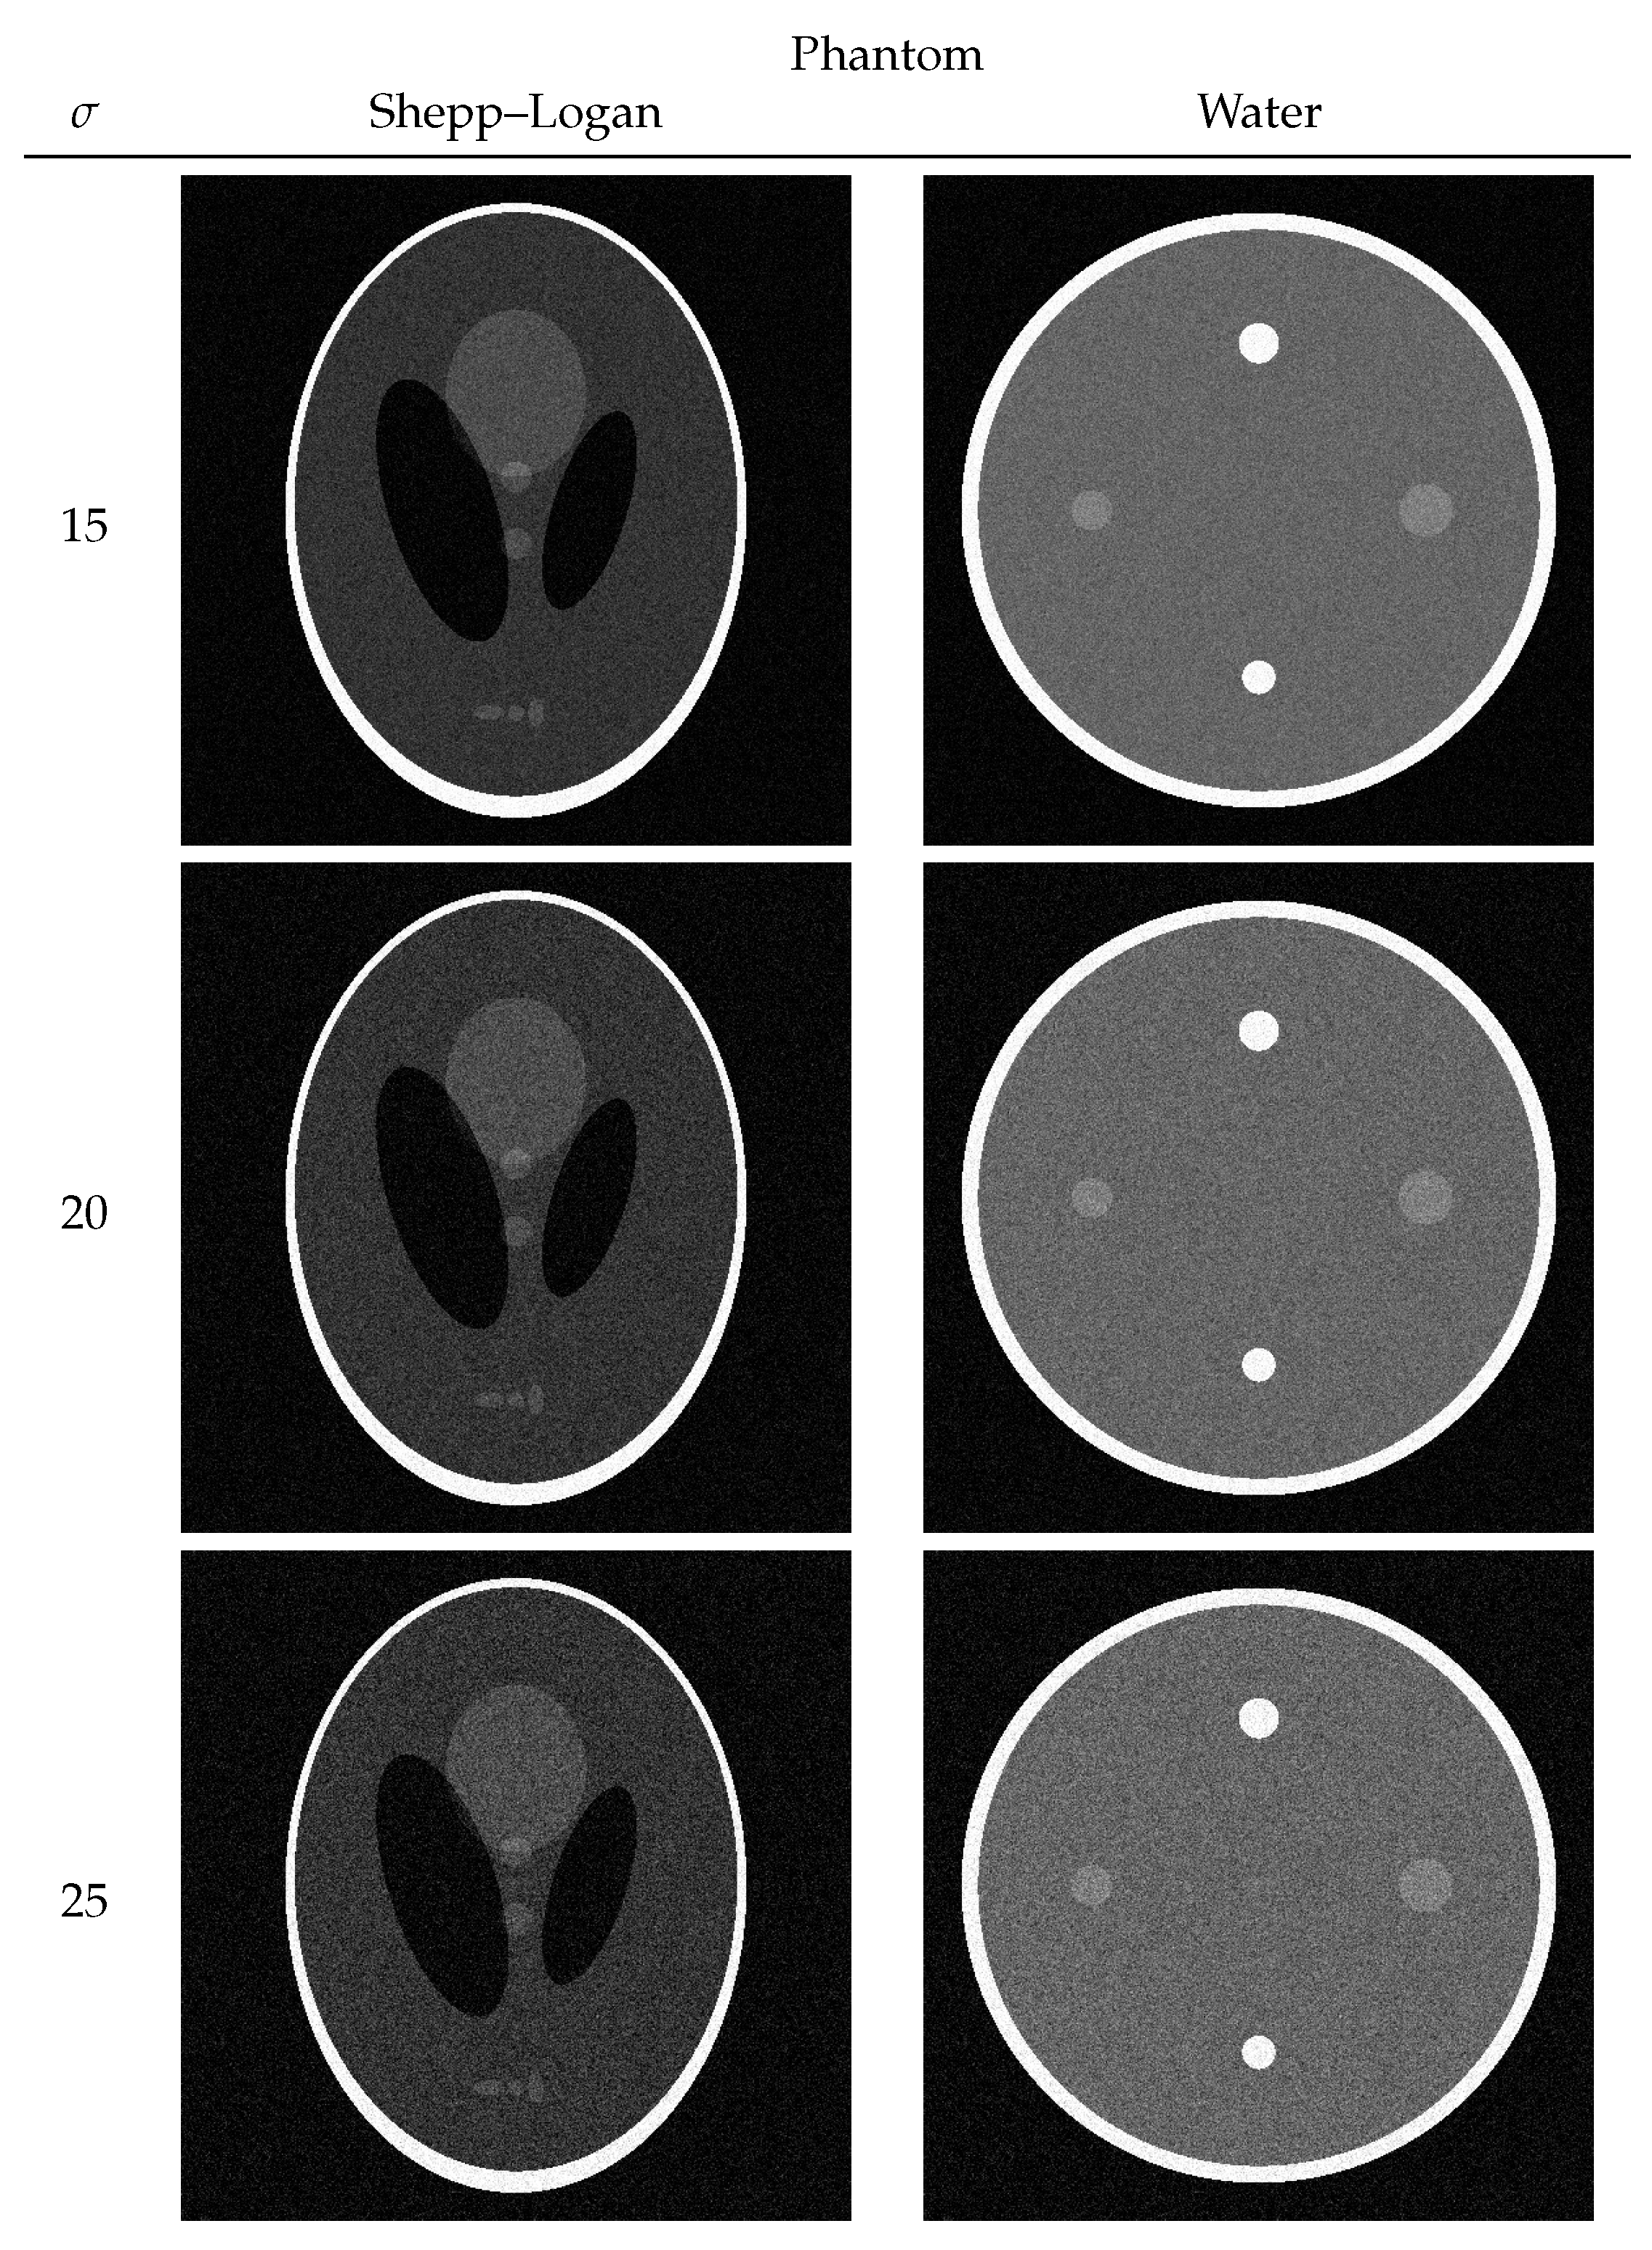

3.1. Numerical Phantom

| 15 | 12.7817 | 90 | 12.3518 | 116 |

| 20 | 13.0832 | 60 | 12.6728 | 66 |

| 25 | 13.3065 | 42 | 12.8896 | 46 |

| 15 | 0.7331 | 0.7047 | 0.6781 | 0.6298 |

| 20 | 0.7130 | 0.6826 | 0.6431 | 0.5556 |

| 25 | 0.6968 | 0.6589 | 0.6026 | 0.5198 |